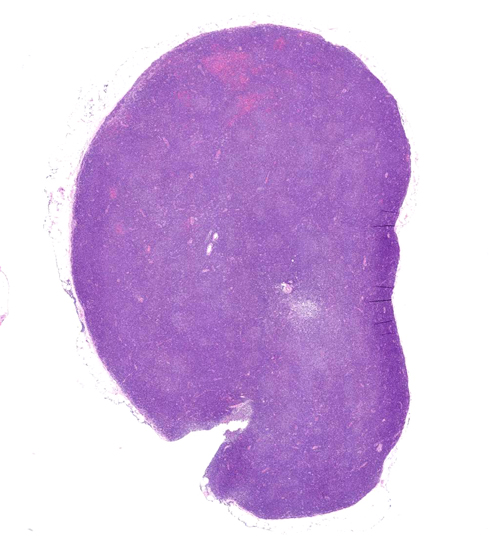

Chronic lymphocytic leukaemia/small lymphocytic lymphoma

CLL/SLL症例01

65歳男性

いびきがひどく, 他院耳鼻咽喉科を受診する。睡眠時無呼吸症候群と診断されて治療をうけていたところ扁桃腫大が認められ当院を紹介され受診する。扁桃および咽頭腫大, 頸部リンパ節腫脹あり。扁桃,上咽頭の生検では腫瘍病変なし。末梢血でWBC11300/μl, lymphocyte 71.3%, LDH180, sIL-2R 1550, 悪性リンパ腫が否定できず頸部リンパ節生検を行った。

頸部リンパ節では, 正常構造は消失し, びまん性小型リンパ球の密な増殖ありproliferation center様構造が散在する。CD20,CD19,CD5,CD23,CD25陽性。cyclinD1陰性。lambda light chain 陽性細胞98%, 核間期細胞FISHで13q14.3単一シグナルが38%の細胞に検出(monosomy 13)された.

Virtual Slideを見る--->頚部リンパ節